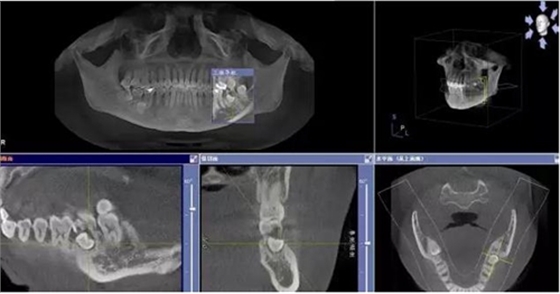

圖1.術(shù)前的CBCT檢查:37頰側(cè)部分牙根被完全壓迫吸收。